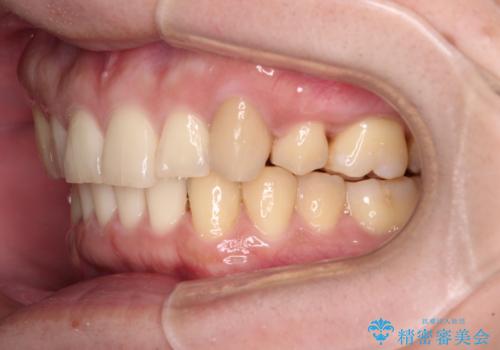

- 上顎の八重歯と前歯のデコボコを気にして来院された患者様です。

八重歯の移動量が多く、インビザライン単体での治療は困難と判断し、補助装置により八重歯移動後にインビザラインを用いることとしました。

上顎のみの抜歯矯正をインビザラインで行う場合、奥歯の前方移動がインビザラインでは苦手のため、奥歯の咬み合わせが不十分となることがあります。

今回の治療では終了時に奥歯は接触しているものの、接触の程度は物足りないものがある状態でした。今後保定期間に少しずつ奥歯の咬合を改善させていくことになります。